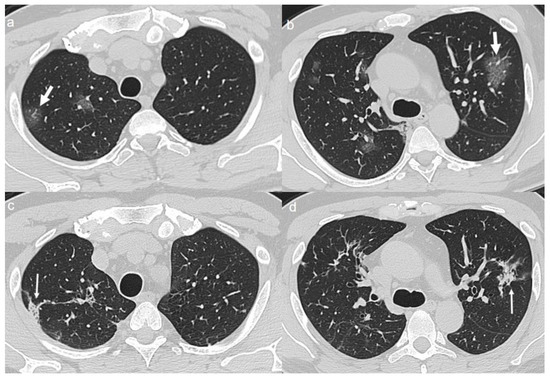

On admission, an unenhanced chest CT showed multiple, rounded ground-glass opacities (GGOs) with peripheral distribution, especially in the right lower lobe (Figure 1a,b).

A chest CT at 4 months from the onset of symptoms showed complete reabsorption of GGOs with no lung abnormalities (Figure 1c,d).

Figure 1. (a,b) CT shows areas of ground-glass opacities (GGO) with peripheral distribution in right lower lobe (arrows). (c,d) CT after 4 months from the onset of symptoms shows complete reabsorption of GGOs with no lung abnormalities.